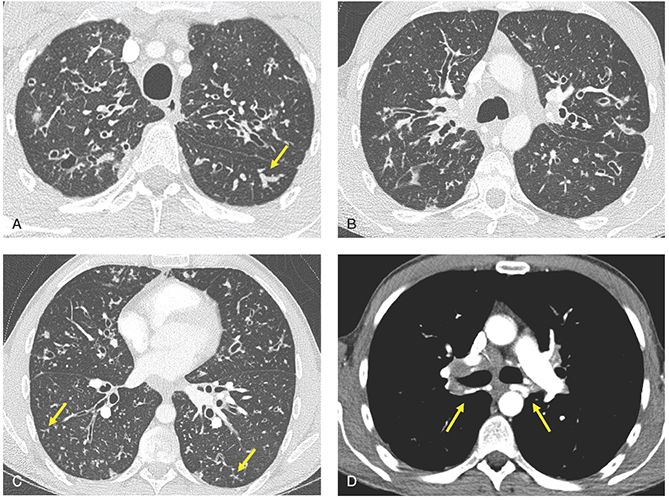

Losing your mucus plug might be a sign you are about to go into labor (childbirth). Plugs Of The Air Passages Chest

The mucus plug serves as protection for the fetus from bacterial infection. Uncomplicated Right Upper Lobe Collapse Mucus Plug Images Diagnosis Treatment Options Answer Review Thoracic Imaging